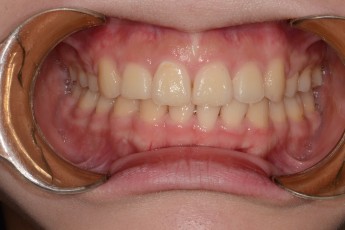

BEFORE & AFTER